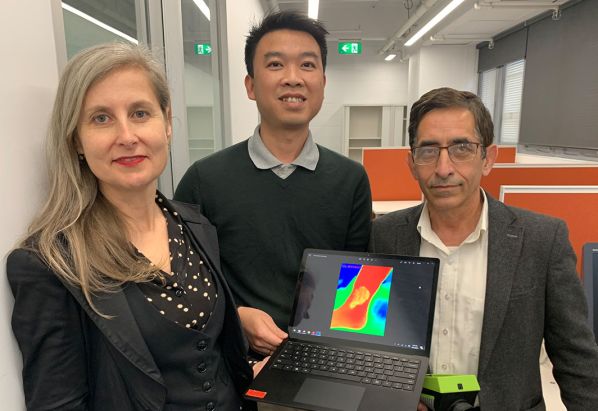

Dr. Rajna Ogrin, Dr. Quoc Cuong Ngo és Dinesh Kumar professzorok

Dr. Rajna Ogrin, Dr. Quoc Cuong Ngo és Dinesh Kumar professzorok